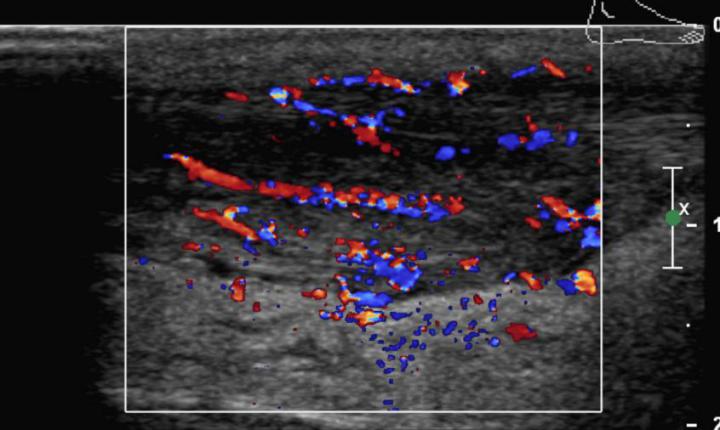

L'injection de facteurs plaquettaires est une nouvelle technique disponible pour le traitement des tendinopahies chroniques, elle doit être pratiquée sous contrôle échographique. La cicatrisation tendineuse est directement dépendante de la vascularisation qui est pauvre au niveau tendineux et qui provient des vaisseaux issus du muscle adjacent essentiellement mais aussi du paratendon et des os.

La faible vascularisation explique le faible potentiel de cicatrisation du tendon, d’où l’idée d’injecter des concentrés plaquettaires dans le tendon qui, grâce à la forte concentration de facteurs de croissance, ont la possibilité d’induire une bien meilleure cicatrisation. Ces phénomènes de cicatrisation peuvent être divisés en trois phases:

Échographie de contraste

Il s’agit d’une méthode d’imagerie associant l’échographie conventionnelle à une injection intraveineuse d’un agent spécifique de contraste permettant une étude dynamique de la vascularisation organique ou lésionnelle. Les agents de contraste utilisés sont des microbulles d’environ 3 microns gardant un caractère intravasculaire strict (Sonovue®Bracco).

Nous utilisons l’échographie de contraste surtout pour caractériser les lésions hépatiques, afin d’éviter dans la mesure du possible des examens IRM ou scanner. Ceci permet aussi souvent de réduire la période angoissante entre la découverte d’une lésion et son diagnostic. L’injection de contraste permet également d’augmenter la sensibilité de l’échographie lors de la recherche de métastases hépatiques ou de néoplasie hépatique secondaire à un cirrhose.